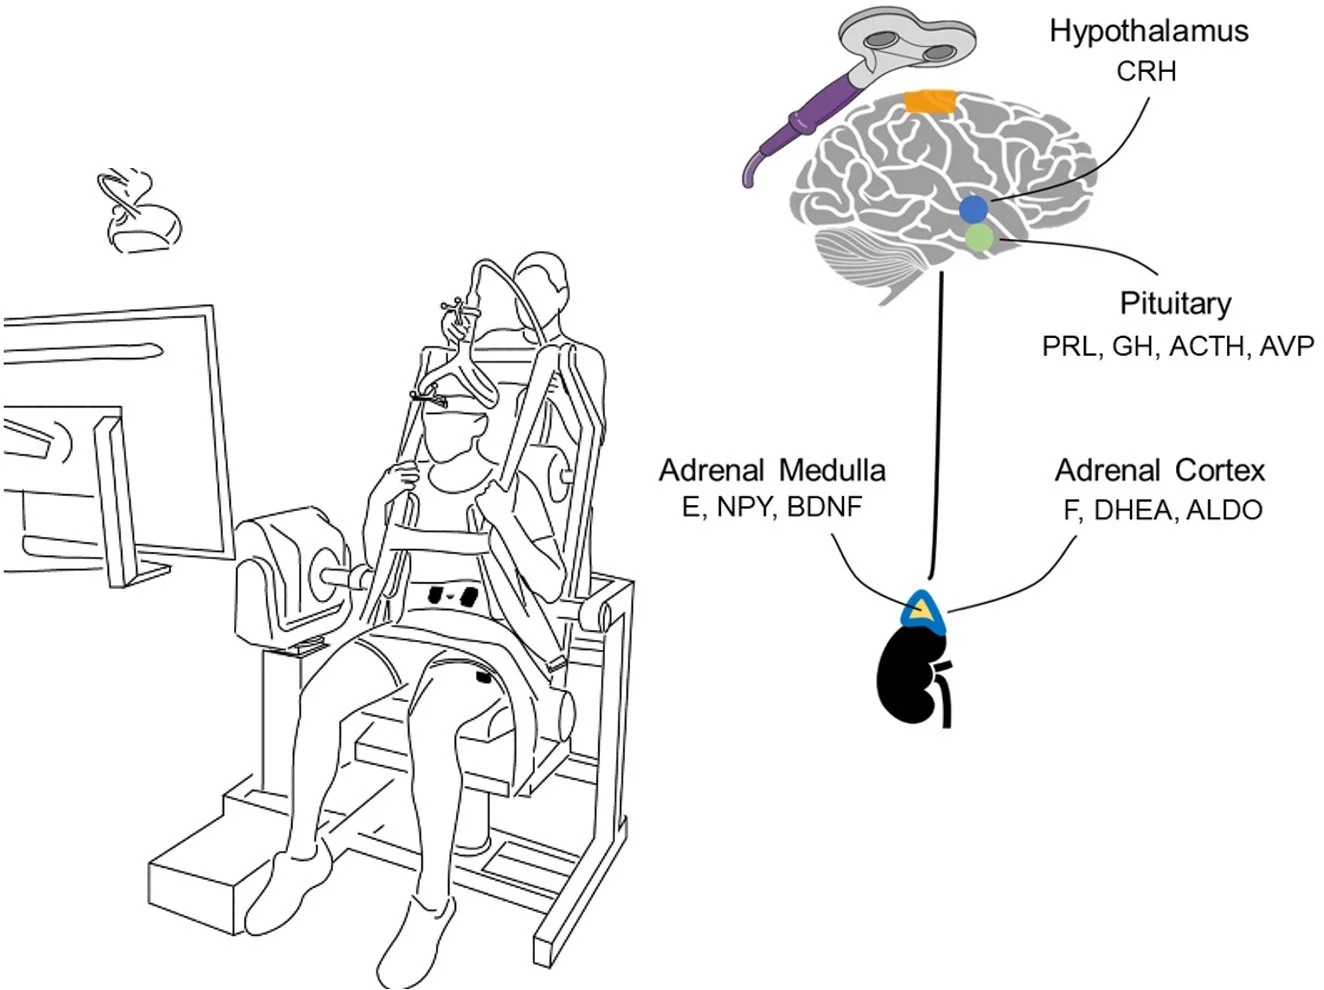

The INBRAIN Laboratory advances human performance through rigorous, innovative, and highly interdisciplinary experimental research. We integrate neuromodulation, multimodal neuroimaging, molecular biology, biomechanics, psychometrics, and wearable sensing to determine how the brain and body adapt to behavior, experience, stress, and injury. Our collaborations across academia, medicine, and the military translate mechanistic insight into actionable approaches that strengthen readiness, enhance recovery, and improve human capability.